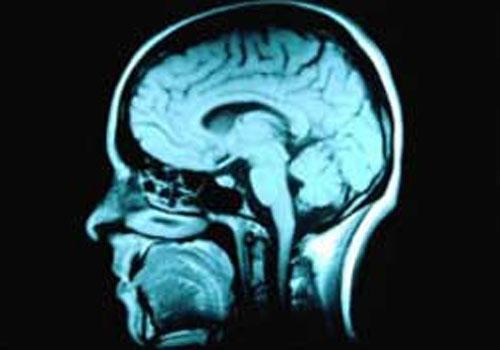

Pornografia pode estar associada a redução da atividade cerebral | Foto: Reprodução

Os voluntários também foram submetidos a um exame de ressonância magnética do cérebro para medir seu volume e observar como ele reagia às imagens pornográficas.